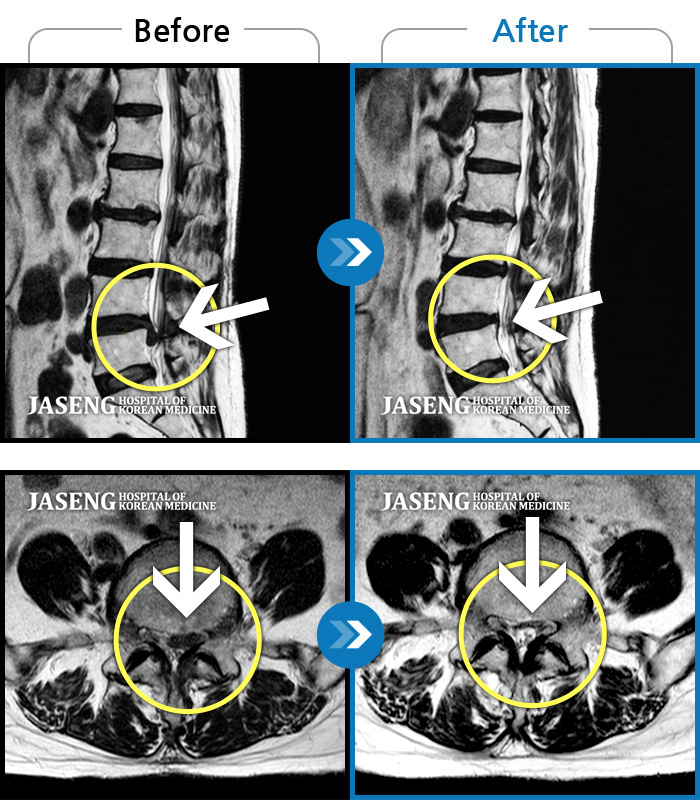

• 허리디스크

• 척추관협착증

• 퇴행성디스크